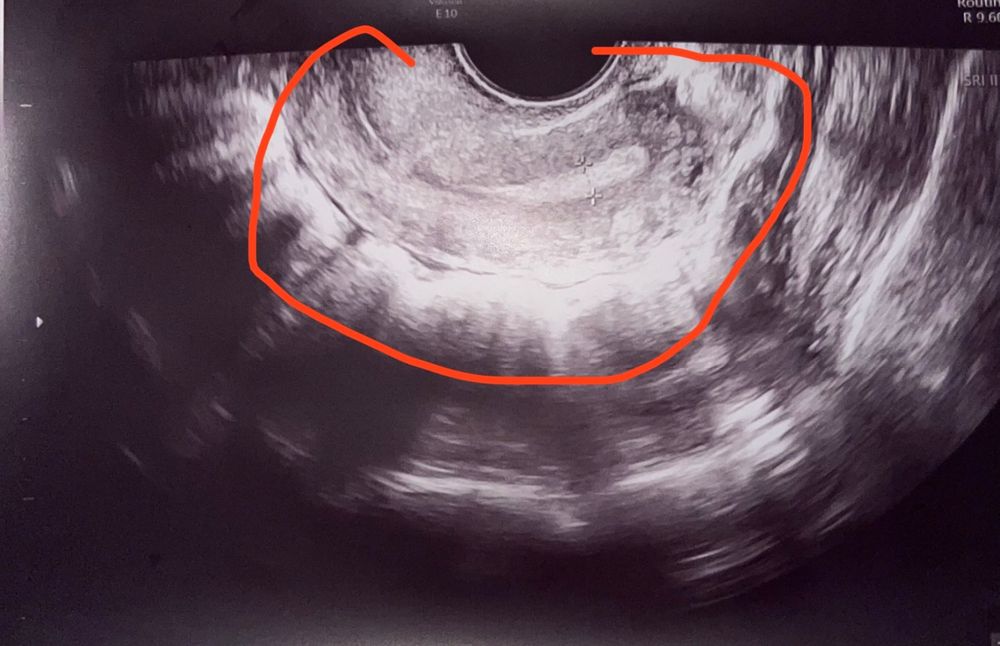

Девушки помогите пожалуйста советом, у меня началась паника тк в этот раз не поймала овуляцию по тестам, но яичники тянули болели, пошла на узи, чтобы исключить кисты на 22 дц, узистка посмотрела про кисты ничего не сказала, отдала узи, сказала жт не нашла, значит овуляции нет, про какие то другие пункты что я спрашивала миомы и тд тоже промолчала, подскажите вот эта дырка может быть кистой, миомой или чем то злокачественным или я зря паникую

На первом фото я так понимаю это матка что я обвела